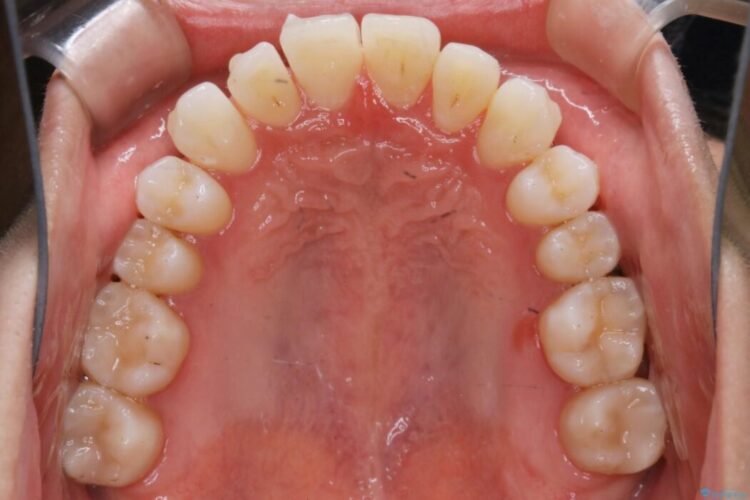

前に出ていた前歯や目立つ八重歯(3番目の歯)もきれいに並び、奥歯の虫歯治療も並行して行ったため、機能面でも見た目的にも良くなり満足していただきました。

非抜歯での矯正治療ではスペースの確保が必要となります。

・歯の遠心移動

・歯列弓の拡大

・IPR(歯の側面を少し削る)

本症例では上記3つの方法を複合的に組み合わせた治療を行いました。